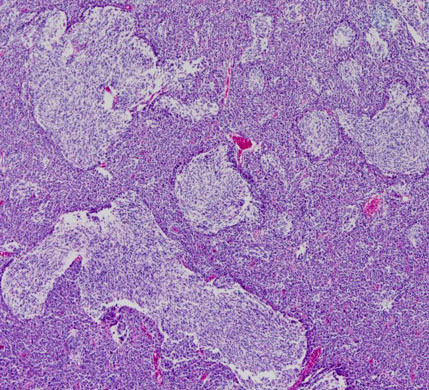

desmoplastic/nodular medulloblastoma

このタイプも治りやすい髄芽腫に分類されています。左がGFAP,右がsynaptophysinです。グリア系への分化を示すGFAPに染まる部分で細胞の増殖力が高くMIB-1の染色率も高いです。島状(結節状)になっていてsynaptophysinで染まる神経細胞への分化を示す部分では,細胞増殖割合は低いです。髄芽腫では神経細胞への分化が観察される分化型のもので治療反応性が良いと考えられます。

左は1歳児に発生した一部に神経芽細胞腫様の分化 row of the tumor cells (or neuronal differentiation) を伴う髄芽腫 medulloblastoma with extensive nodularity(小脳神経芽細胞腫 cerebellar neuroblastomaともいわれたもの)。右は7歳児の退形成(核の異形成)が顕著な退形成性髄芽腫 anaplastic medulloblastomaです。前者の治癒率は高く,後者の病理像の治癒率は極めて低いものです。